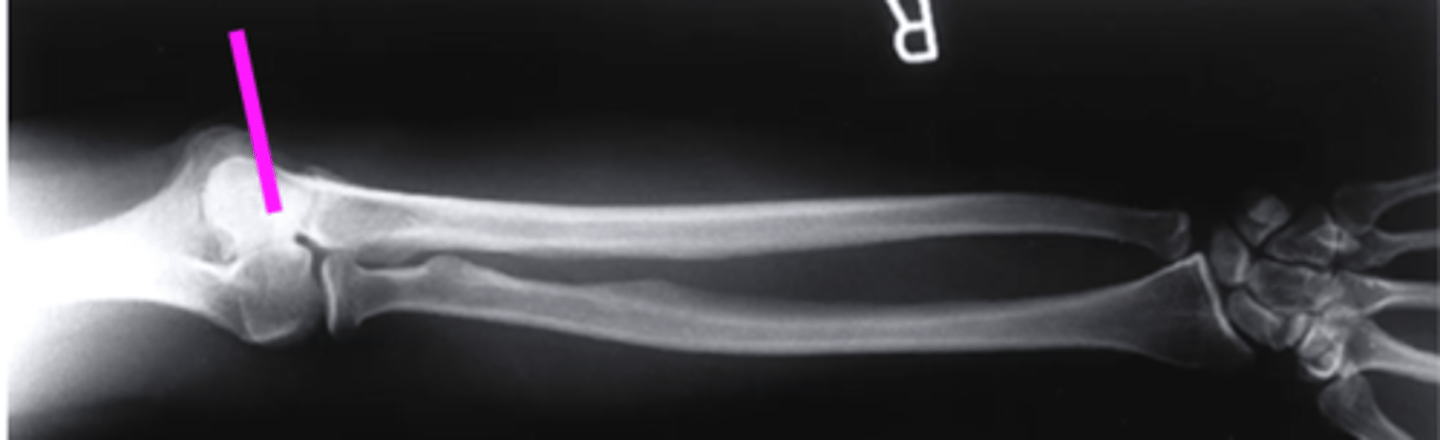

AP forearm

what view is this?

olecranon process

what does this pink line point to?

trochlea

capitulum

humeroradial joint

proximal radioulnar joint

radial tuberosity

radial styloid

distal radioulnar joint

scaphoid

lunate